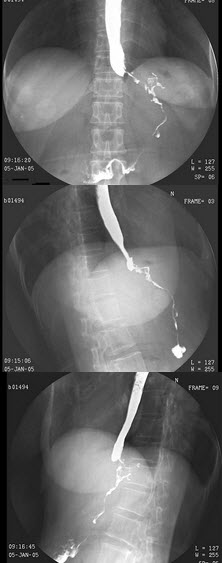

5、单项选择题

女,42岁,双下肢疼痛,结合图像,最可能的诊断是()

A.Paget病

B.内生软骨瘤

C.非骨化性纤维瘤

D.骨巨细胞瘤

E.骨纤维异常增殖症

点击查看答案